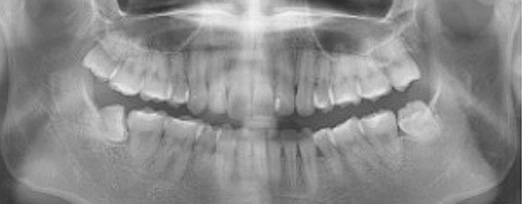

사랑니 발치

최소통증으로, 편안하게!

왜 청담네오플란트에서 사랑니를 뽑아야 할까요?

청담네오플란트는 3D CT 촬영 후 전문의료진들의 정확한 분석으로 안전하게 사랑니를 발치합니다.

매복 사랑니 발치 이젠 두려워하지 마세요!

청담네오플란트치과 사랑니 발치 프로세스

01. CT 촬영

안전하고 통증을 최소화한 발치를 위해 3차원 정밀 분석을 합니다.

02. 정확한 분석

사랑니의 크기와 방향, 깊이, 뿌리 상태 등과 구강검진을 실시합니다.